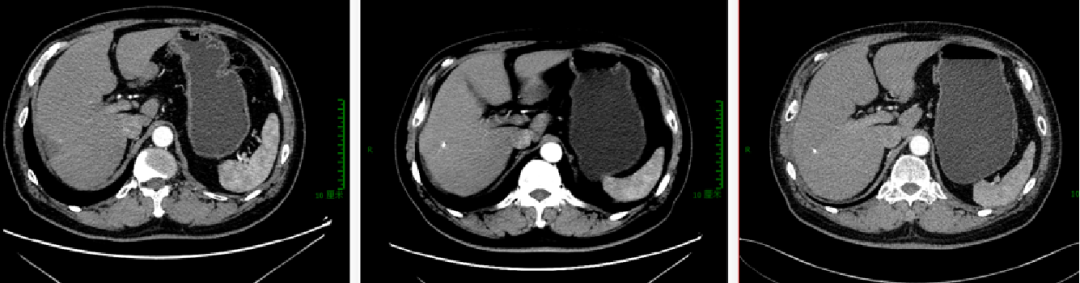

图示:2017-4 “直肠CA根治术+肝转移瘤切除术+胆囊切除术”后改变,直肠吻合口旁肠壁稍增厚;肝右后切缘旁低密度灶,较前片(2016-12-13)有所缩小,请结合临床并随访。

2017-4 我院PET-CT未见明确复发转移病灶:吻合口未见FDG代谢异常,肝右叶转移瘤术后,残余肝实质内FDG代谢未见异常,两肺野多发微小结节影,FDG代谢未见明显增高,考虑良性。